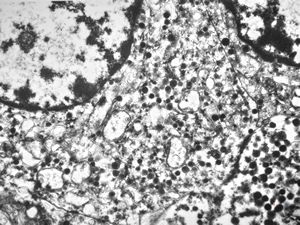

F, 45y. | carcinoid … liver metastasis